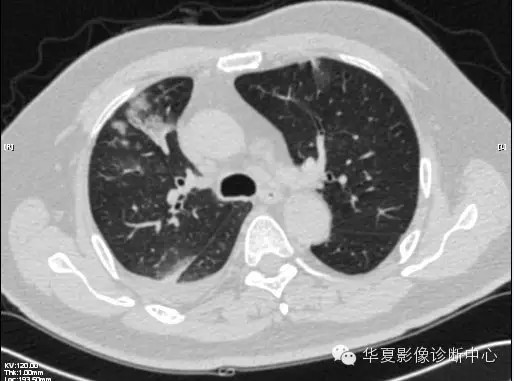

【病例学习】甲型H7N9禽流感一例

男性 63

发热咳嗽5天

2013-4-5拍片示右肺实变,收入院,追问病史,发病期间肌肉酸痛,头痛,无腹痛腹泻,无明显胸闷气急,无意识改变。有高血压病史,无其它病史。

2013-4-7CT进一步检查。

最终诊断:H7N9。